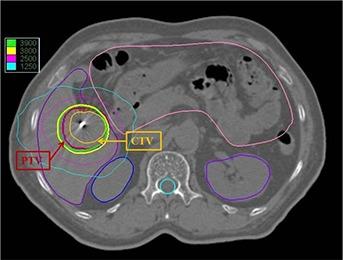

Prolonged treatment execution time is a concern in CyberKnife robotic radiosurgery. Beam reduction and node reduction technique, and monitor unit optimization methods are adopted to reduce the treatment time. Usage of single collimator in the CyberKnife treatment plan can potentially reduce collimator exchange time. An optimal single collimator, which yields an acceptable dose distribution along with minimum number of nodes, beams, and monitor units, can be a versatile alternative for shortening treatment time. The aim of the present study is to find the optimal single collimator in CyberKnife treatment planning to shorten the treatment time with the acceptable dose distribution. A spherical planning target volume PTV1 was drawn in an anthropomorphic head and neck phantom. Plans with same treatment goals were generated for all the 12 collimators independently. D(95%) was selected as the prescribing isodose and the prescribed dose was 10 Gy. The plan of the optimal collimator size was evaluated for conformity, homogeneity, and dose spillage outside the target. The optimum collimator size and the target dimensions were correlated. The study was repeated with two other target volumes PTV2 and PTV3 for generalizing the results. Collimator sizes just above the diameter of the spherical PTVs were yielding least number of nodes and beams with acceptable dose distributions. The collimator size of 35 mm is optimum for the PTV1, whose diameter is 31.4 mm. Similarly, 50 mm collimator is optimum for PTV2 (diameter= 45.2 mm) and 20 mm collimator is optimum for PTV3 (Diameter = 17.3 mm). The total number of monitor units is found to reduce with increasing collimator size. Optimal single collimator is found to be useful for shortening the treatment time in spherical targets. Studies on two clinical targets, (a brain metastasis and a liver metastasis cases) show comparable results with the phantom study.

在 CyberKnife 机器人放射外科中,治疗执行时间延长是一个关注点。可以采用减少射束和节点数量以及优化监测单位的方法来缩短治疗时间。在 CyberKnife 治疗计划中使用单个准直器可以潜在地减少准直器更换时间。一个最佳的单准直器,可以产生可接受的剂量分布,同时具有最小数量的节点、射束和监测单位,是缩短治疗时间的多功能替代方案。本研究的目的是在 CyberKnife 治疗计划中找到最佳的单准直器,以在可接受的剂量分布下缩短治疗时间。在人体头颈部模型中绘制了一个球形计划靶区(PTV1)。为每个 12 个准直器独立生成具有相同治疗目标的计划。选择 D(95%)作为规定等剂量线,规定剂量为 10 Gy。评估了最佳准直器尺寸的计划的适形性、均匀性和靶区外剂量泄漏。对目标尺寸和最佳准直器尺寸进行了相关性分析。对另外两个靶区 PTV2 和 PTV3 进行了研究,以推广结果。直径略大于球形 PTV 直径的准直器可产生具有可接受剂量分布的最少节点和射束数量。对于 PTV1(直径为 31.4mm),35mm 的准直器是最佳的;对于 PTV2(直径为 45.2mm),50mm 的准直器是最佳的;对于 PTV3(直径为 17.3mm),20mm 的准直器是最佳的。随着准直器尺寸的增加,监测单位的总数减少。研究表明,对于球形靶区,最佳的单准直器可用于缩短治疗时间。对两个临床靶区(脑转移和肝转移病例)的研究结果与模型研究相似。